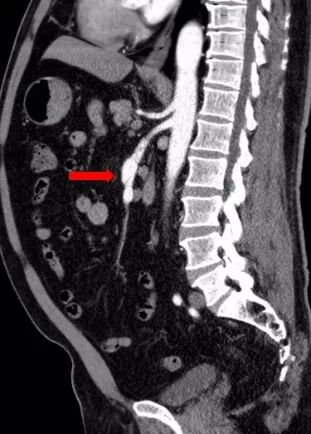

术前查腹腔动脉CTA示:肠系膜上动脉夹层伴动脉瘤。

患者肠系膜上动脉夹层动脉瘤,真腔明显缩小,假腔增大,有胃肠道缺血表现,有手术指征,未见手术禁忌。

术前造影图像